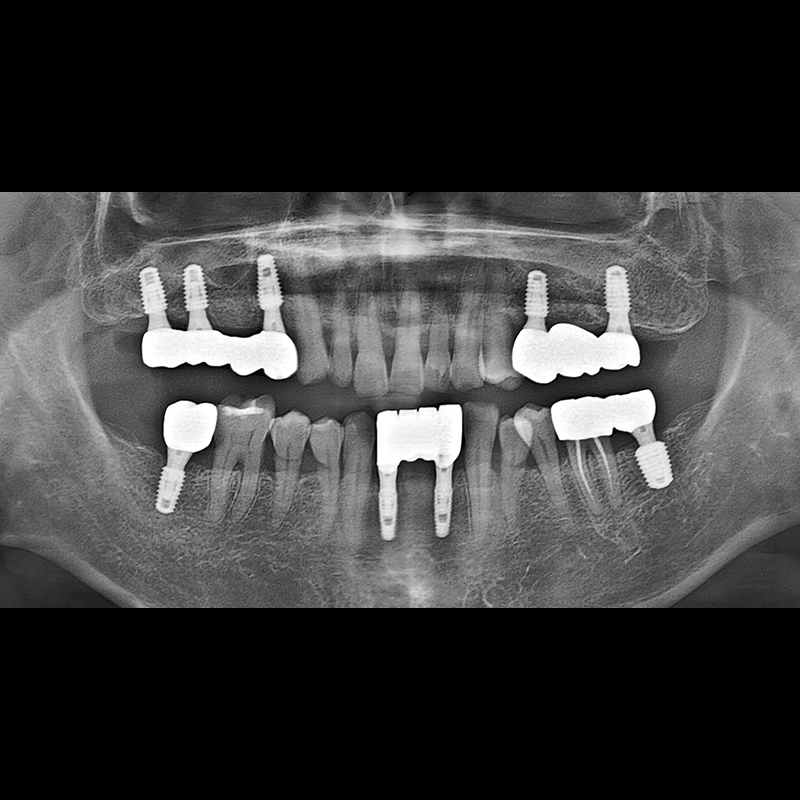

BEFORE AFTER

임플란트 전후사진 2025.05.30

결손된 치아 부분과 살리기 힘든 치아 위치에 임플란트를 식립하였습니다.